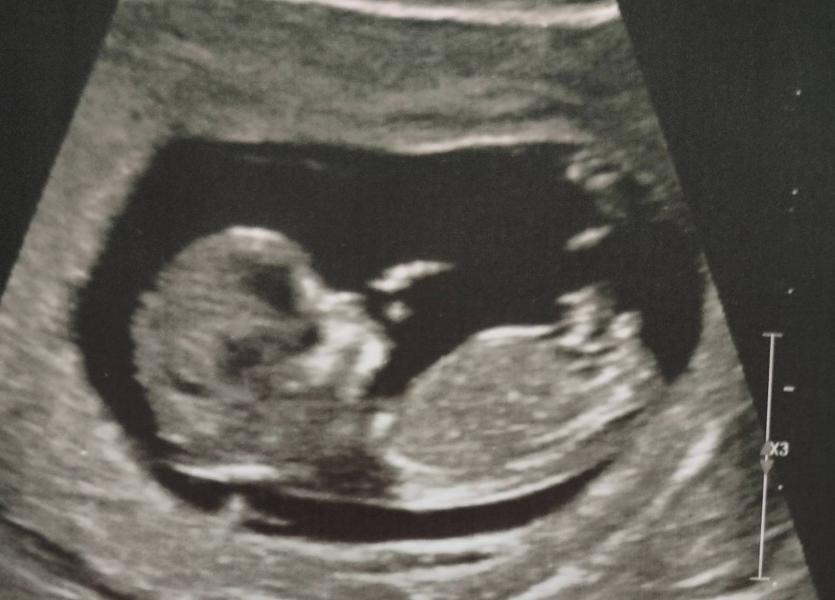

Вот и 1 скрининг прошел, все хорошо у нас🤗

Ручкой мне помахал(а)🥰

Девочки, то что вы принимаете за пол, это не оно))

В 12 недель ещё нет явных признаков, только половой бугорок определенного наклона)

Мальчик у вас🥳🙌🏻

На мальчика похоже)